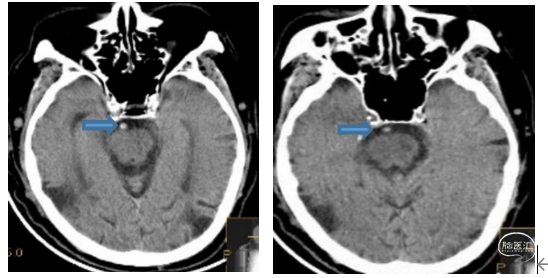

患者男性,76岁。“突发头晕5小时,昏迷3.5小时”急诊入院。既往高血压病史。查体:昏迷,四肢瘫,NIHSS评分35分。术前影像:CT平扫见基底动脉高密度征。

造影显示左侧椎动脉为优势血管,基底动脉闭塞部位呈笔尖征,结合临床症状提示ICAS病变(下图1、2)。首过效应阳性(下图3),释放4×30mm Syphonet®取栓支架,可见支架通体显影(下图4),支架中部呈现蜂腰征,辅助判断病变部位。